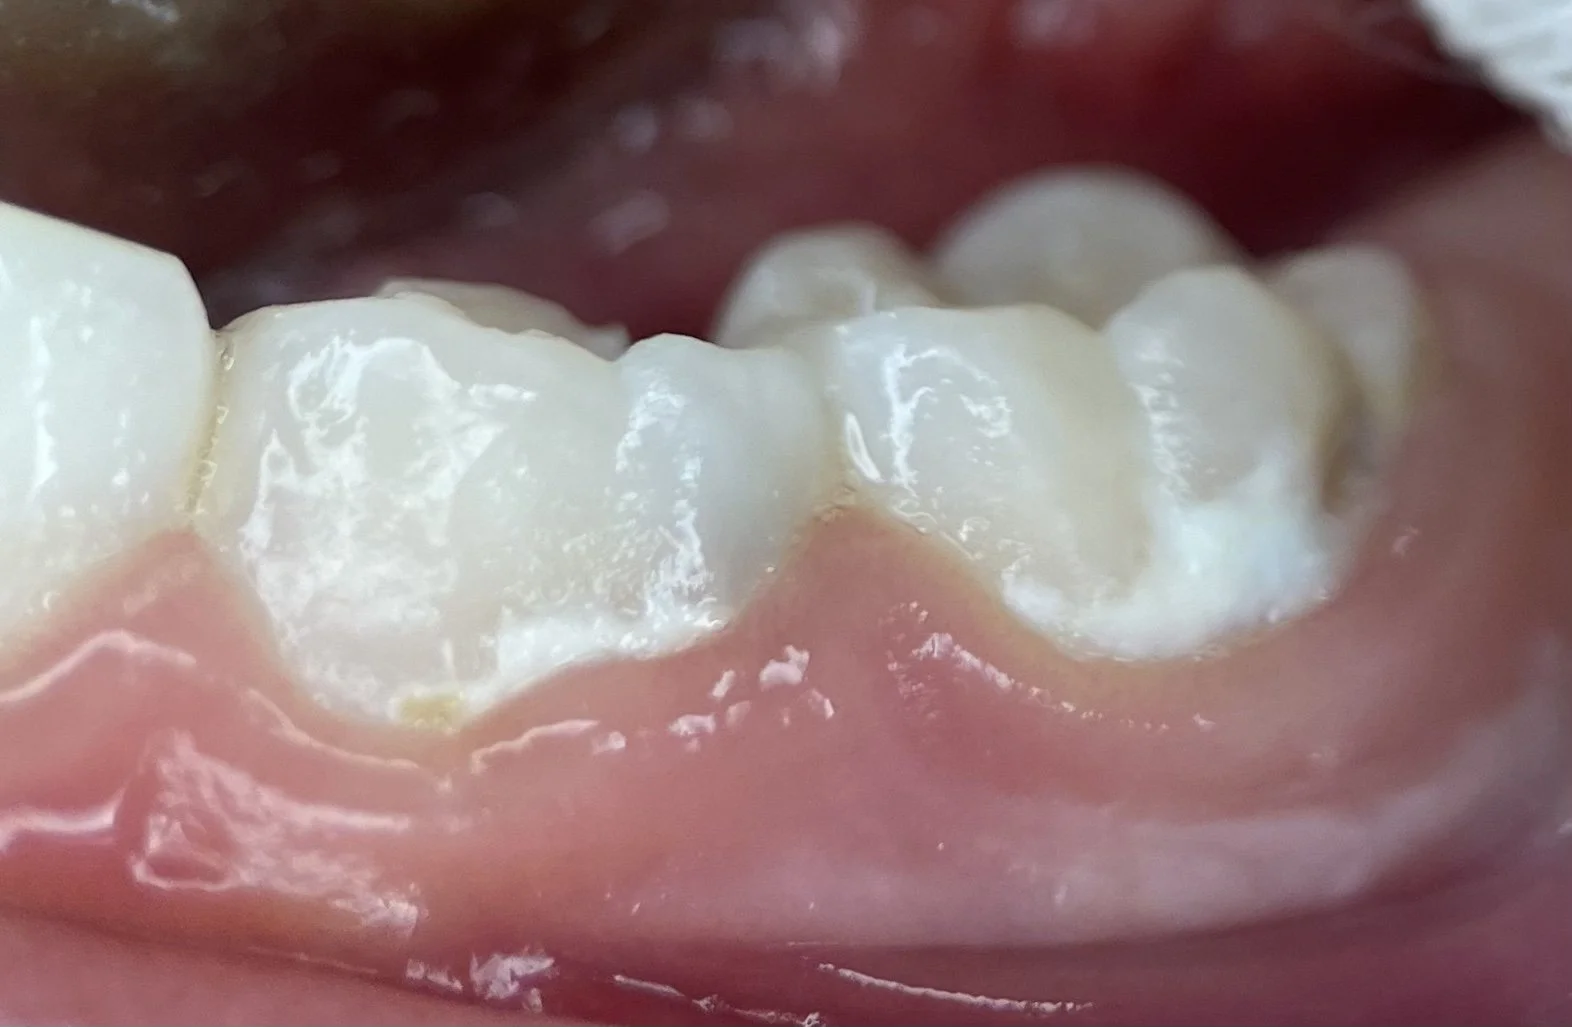

These are the teeth of a 24 month who breast feeds on demand. Other than breast milk, this child only drinks water and eats a healthy diet of fruits, veggies, meats, but limits sugar-ladened foods.

If you start to see white marks along the gum line (as pictured above), this is the start of cavities. Dental cavities are a result of many factors. If you see this, contact your local dentist or pediatric dentist.